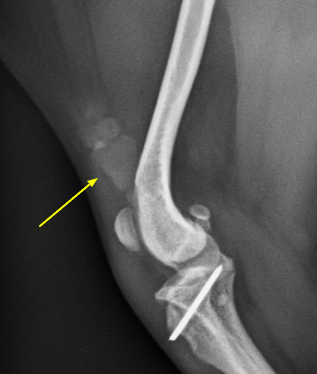

근육 석회화를 유발할 수 있는 질환

- 근육 질환

- 급성 또는 만성 근육 손상

- 석회화 힘줄염

- 외상